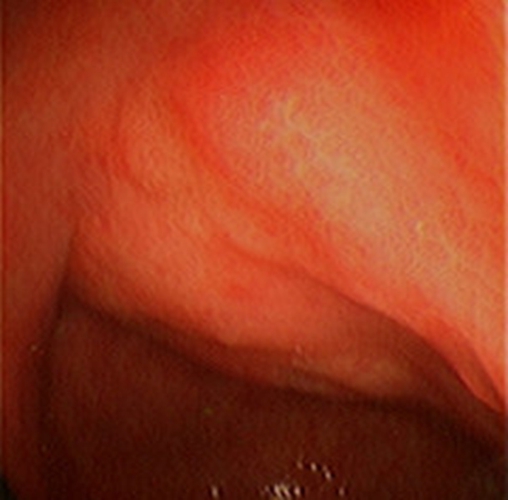

急性胃炎圖片

急性胃炎陽性表現

急性胃炎陽性的表現的

急性胃炎陽性的表現

急性胃炎陽性表現的

急性胃炎的陽性的表現的

急性胃炎的陽性的表現